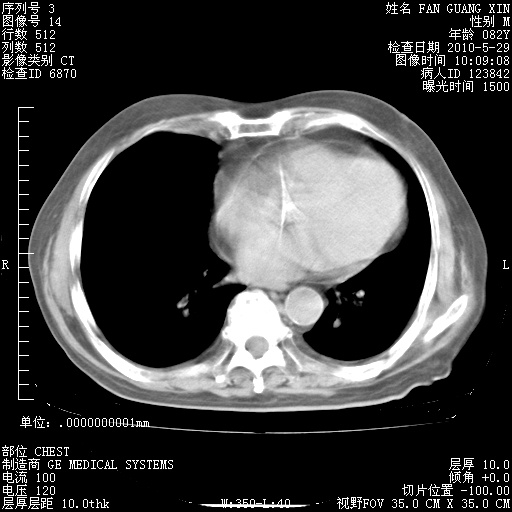

治疗3周后的肺部CT纵隔窗

再治疗10天后的肺部CT